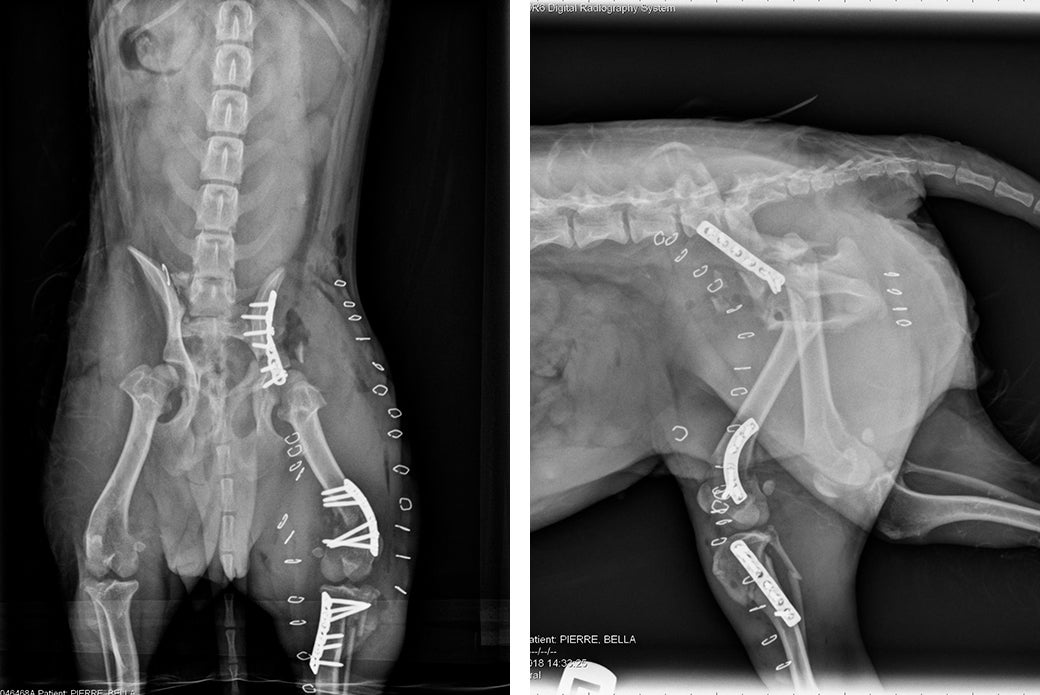

Post-op radiographs show the extent of Bella’s fractures and where Dr. Gayle made repairs.

“She had obviously undergone extensive trauma,” says Dr. J’mai Gayle, Director of Surgery at the AAH. “Both sides of her pelvis were fractured, as well as her left tibia and left femur. We also diagnosed nerve damage on her right side.”

Dr. Gayle performed a four-hour surgery to repair Bella’s fractures. Following surgery, veterinarians were still concerned that the extent of Bella’s injuries might result in a necessary amputation of her left hind leg.